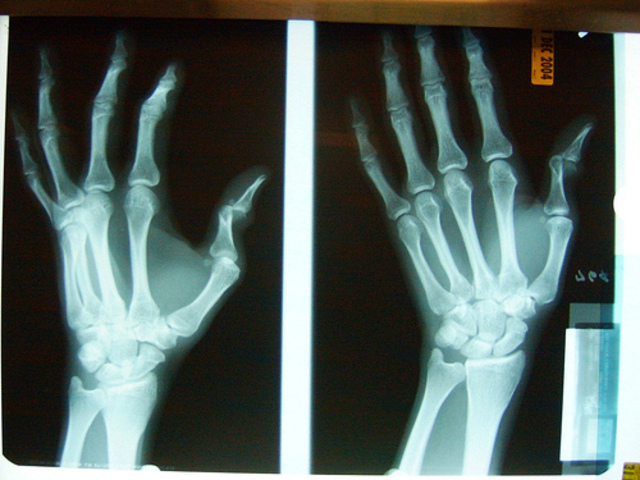

• Broke Both Wrists Jumping From Swing

Broke Both Wrists Jumping From Swing

This was childhood because I saw Megan daring me to jump and I did this in the 1st grade to impress her! This was part of my preoperational stage, because I didn't think this 1 through at all.